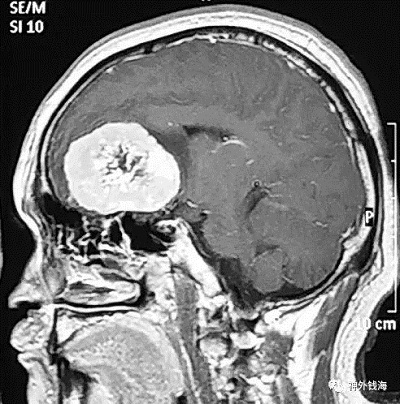

在临床工作中,我经常遇见这样的情况:患者视力一直不好,在眼科检查治疗了很长时间也不见效,眼科也的确没有发现异常情况。还有的患者月经紊乱,或者不孕不育,在妇产科及内分泌科治疗了一段时间,也是没有效果。后查了头部的核磁共振,才发现原来病因在颅内,鞍区已经有了一个很大的肿瘤。手术切除肿瘤以后,原来的眼睛或内分泌问题也逐步恢复了。这就是特别需要引起重视的,即颅内肿瘤可能表现为眼科或妇产科、内分泌科的疾病,如果忽略了头部检查,则可能遗漏了根本的病因,因而疗效只会是暂时的,或者是“久治不愈”。

尽管颅内肿瘤相对于眼科疾病、妇产科疾病及内分泌科疾病的发病率低,相对少见,但是在神经外科住院患者中,很大一部分患者以此为主要症状或首发症状。磁共振检查对人基本无损伤,无放射性,可以有效检查出上述颅内疾病。

首都医科大学三博脑科医院神经外科钱海特别提示眼科、妇产科及内分泌科的患者,如果遇到上面所说的情况,特别是伴有头痛的患者,请在医生指导下进行头部磁共振检查,可能会找到疾病的源头,从而达到满意的疗效。